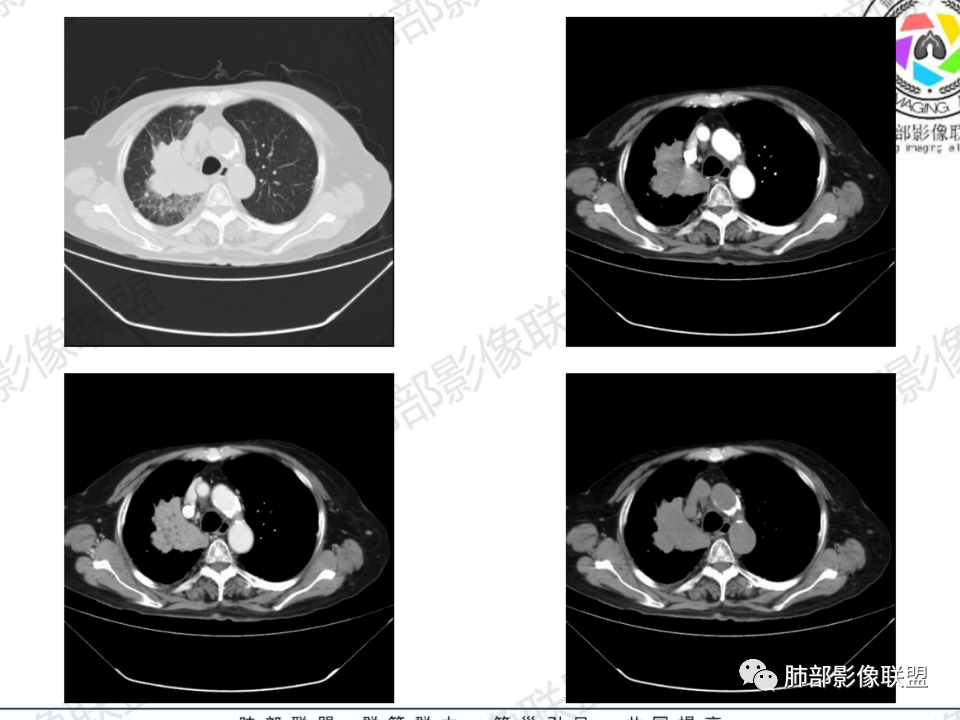

临床信息:老年女性,亚急性病程,咳嗽发热。有激素使用史。既往有淋巴结结核病史。肿瘤标记物Ca125升高。血沉升高,C反应蛋白轻度异常。 影像所见:右侧胸廓相对狭小,右肺上叶不规则团块影贴附纵隔旁,轻度分叶,整体密度较均匀,偶见钙点。

相应上叶尖端及前段支气管开口未能追踪(阻塞),开口处见钙化。病灶渐进性强化,并衬托出较完整尖段及前段含液支气管影。支气管开口区域未见异常高密度强化(如类癌等)及相对乏血供区(如鳞癌)。病灶区未见液化坏死。右上纵隔及胸廓入口区未见病灶胸膜外突破(栽赃)。

右肺上叶后段等区域散在片状影,边界不清(提示渗出性病灶)。

纵隔及双肺门见钙化淋巴结。心包积液,右侧胸腔积液(提示存在活动新病灶)。双侧胸膜下见多发斑点状钙化,胸廓变形(提示存在结核基础病变可能)。 诊断意见:综上,右肺上叶块状影更符合继发性肺结核。 最后小结:既往诊断淋巴结结核,提示已治愈。近2年服用激素,可疑诱导结核复燃,也可引起发热。纵隔肺门淋巴结肿大钙化,压迫支气管,右肺上中下叶支气管均狭窄,所以引起喘息咳嗽。尖段支气管受累闭塞,导致肺不张、支气管粘液栓,出现条状无强化区。病变累及胸膜,导致结核性胸膜炎并胸水,引起右侧胸痛。实验室检查血沉快,CA125高,低蛋白,均符合结核。下一步,建议支气管镜尖段支气管刷检并抗酸染色。(本段摘自於雄老师精彩发言)